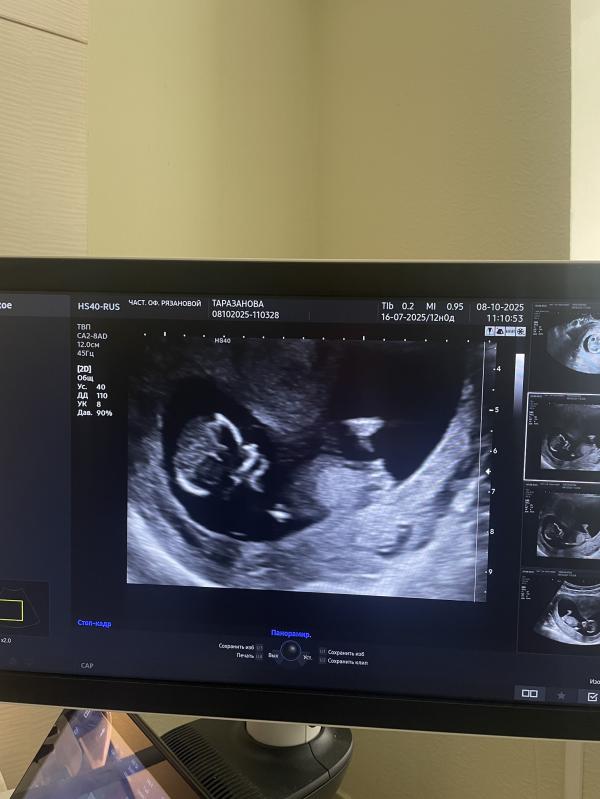

Ну вот и первый скрининг прошёл🙏☺️

По узи 12.4 недели 🩷

Так рада была встретиться с малышом,такой большой уже🙏

Поздравляю вас🍾 Я тоже сегодня скрининг первый прошла)

И у меня сегодня первый скрининг ❤️ 12.4 недели

ПДР 18.04.26г

Жду результат крови

По узи сказали мальчик)